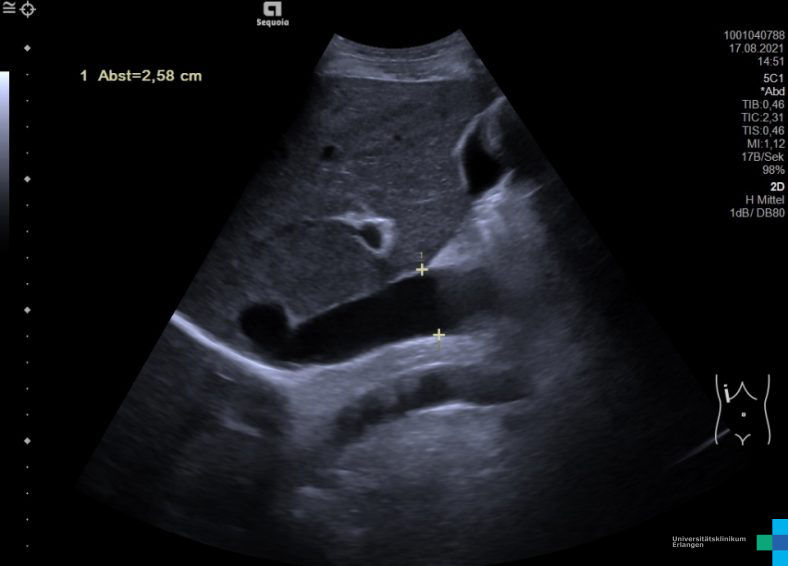

GLY_VEN_VCI_1325.jpg